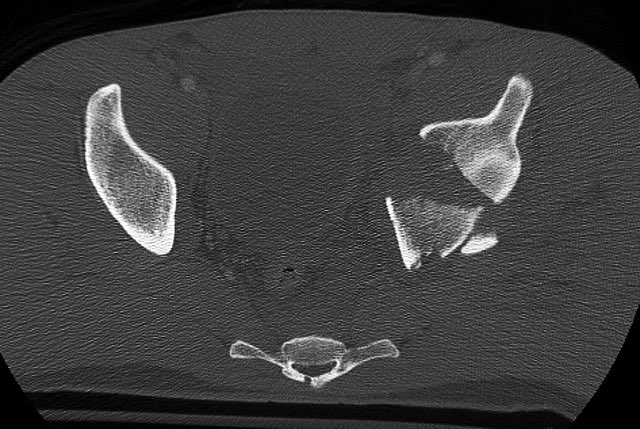

The axial dome image

We used a regular table and an Ilioinguinal exposure to first reduce and stabilize the PC fragment to the intact ilium

Then reduced and clamped and stabilized the dome AC fragment

Then finished up the rest